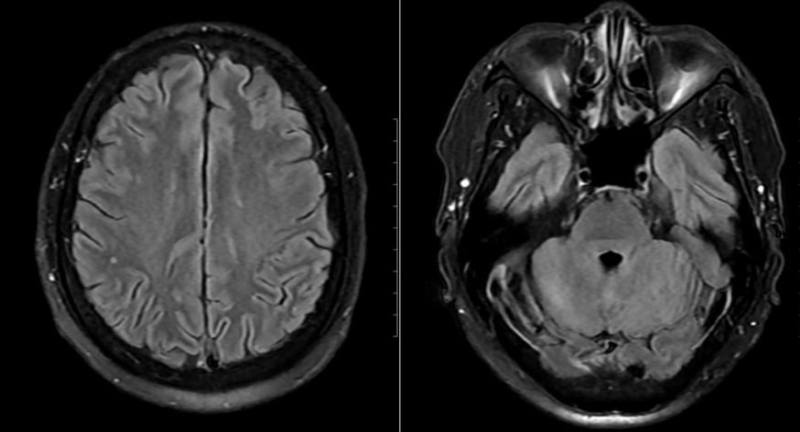

Thần kinh

nếu không được chẩn đoán và điều trị kịp thời, khiến nặng thêm như các bệnh lý tim mạch, huyết áp, rối loạn điều chỉnh cảm xúc, suy giảm trí nhớ, suy giảm chức năng sinh lý của cơ thể. Chuyên khoa Thần kinh, Bệnh viện Đa khoa MEDLATEC là địa chỉ uy tín khám và điều trị các bệnh lý thần kinh, tâm thần với cam kết chính xác, chất lượng và đa dạng dịch vụ tiện ích.